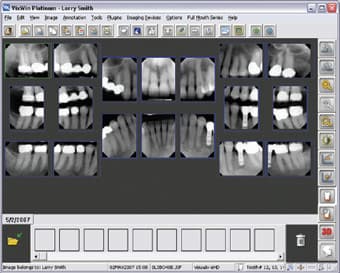

Digital Imaging—Life-Changing Technology

Digital imaging is part of efficient communication, and it adds to the “wow factor.” Patients may see their teeth in the mirror every day, but we must supply images that will let them learn about improving their dentition. For this, digital radiography has become the standard of care in diagnostics. This technology provides superior-quality images in a couple of seconds. It is an excellent diagnostic aid with which to compose a treatment plan. On the screen, we can enhance or zoom in, invert or emboss an image to communicate the possibilities in an unobtrusive way. Sometimes a patient may have a problem such as a fractured restoration that cannot

Digital Imaging – It’s a Win-Win for Everyone!

When patients are educated about the details of their dental health, they are more likely to understand the value of treatment. In my quest to improve my patients' dental experience, about two years ago, I began to explore the various options for digital radiography. At first, I was apprehensive about going digital and how this would affect workflow. After a short training period with my staff, I was happily convinced-digital-imaging advancements improve patient care. One very apparent positive aspect of digital imaging is connected with my imaging software-it both makes my job easier and involves the patients in their own treatment. This easy-to-use imaging software captures and mounts X-rays, offers

Digital Radiography : Don’t Miss Out!

I'm always perplexed by some of hygiene friends who say they don't have digital radiography yet because either the office isn't ready or that their doctors feel it's too expensive. As a hygienist who has seen the light that digital brings to a practice, I see it as my personal mission to help convert these offices. They just don't know what they're missing! When I ask a hygienist what "not ready" means to her and to her office, I hear things like, "We're not looking forward to the 'big' change."..."We don't have computers in the operatories yet."...and "We don't think our patients will take to it." They